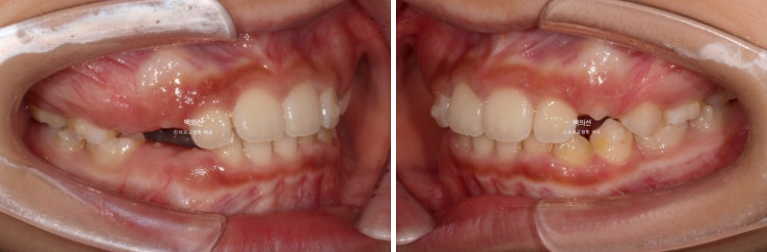

24.11

9개월 후 모습을 보면 송곳니와 작은어금니들이 많이 올라온 게 보입니다.

이제 슬슬 재제작을 할 타이밍입니다.

2024년 11월에 재제작을 시작, 24년 12월부터 재제작한 장치를 끼기 시작했습니다.